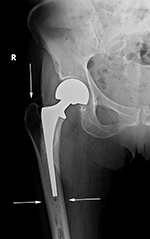

| 69 year-old woman with right femoral neck fracture treated with bipolar hip prosthesis (left image). Five months later (right image) there is reduction of femoral cortical thickness (lower two arrows) and osteopenia in the greater trochanter (top arrow) from stress shielding. |